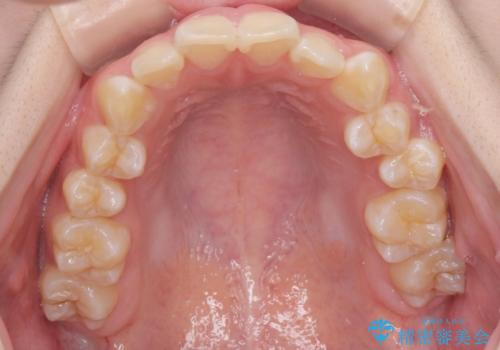

- 前歯のがたつきが気になるとの事で来院。

マウスピース矯正希望でしたのでインビザラインモデレートで治療を行いました。

がたつきが無くなり満足して頂けました。